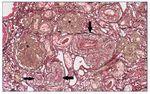

Con el diagnóstico de síndrome nefrítico, se realizó biopsia renal percutánea. La muestra incluía 34 glomérulos por sección, 25 de ellos (73%) globalmente esclerosados con restos de material hialino. De los 7 glomérulos restantes, 2 no mostraban alteraciones relevantes (fig. 2), mientras que los demás presentaban intensa proliferación endocapilar segmentaria o, más frecuentemente, global con ocasional cariorrexis y marcada hiperplasia/ hipertrofia del epitelio visceral (podocitos), con formación de seudosemilunas (figs. 3 y 4). No se identificó colapso de los capilares glomerulares ni lesiones en el polo tubular de glomérulos. Los podocitos hiperplásicos mostraban signos de reabsorción proteica y, además, se apreciaban áreas de adherencia flóculo-capsular en 2 de los glomérulos (fig. 5). También se apreciaban amplios parches de atrofia tubular, con intenso infiltrado inflamatorio acompañante y fibrosis intersticial, por lo general coincidiendo con glomérulos esclerosados, que suponen aproximadamente un 40% del área cortical. De forma ocasional se observaban túbulos dilatados con contenido proteico y/o hemático. No se identificaron depósitos hialinos en las paredes arteriolares, pero todas ellas mostraron una llamativa hipertrofia concéntrica de la capa muscular con marcada reducción y casi obliteración de la luz capilar (fig. 6). Las arterias interlobulares/ arcuatas mostraban menor grado de hiperplasia que la media sin alteraciones significativas de la íntima. No se observaron focos de necrosis fibrinoide ni trombos capilares en los glomérulos ni en las arteriolas. En el estudio de inmunofluorescencia directa se apreciaban únicamente depósitos glomerulares irregulares de IgM (1+) y C3 (2+) (fig. 7). Se realizó estudio de microscopia electrónica a partir del material incluido en parafina, y los hallazgos fueron de valoración limitada debido a la mala preservación tisular. Seis de los 7 glomérulos de la muestra se encontraban globalmente esclerosados y el restante mostraba esclerosis segmentaria; en su zona no esclerosada se observó pérdida de integridad de los endotelios y pérdida parcial de integridad de las células epiteliales viscerales, con intensa fusión de los pedicelos en las áreas mejor conservadas (fig. 8). La falta de integridad de las paredes capilares no permitía una medición correcta de su grosor, aunque, en las láminas densas conservadas se apreciaban algunas irregularidades y algunas laminaciones, así como zonas de menor grosor y zonas de mayor severidad en el espesor de la membrana de la lámina densa. No se observaron depósitos electrón-densos. Con estos hallazgos se diagnosticó de glomeruloesclerosis focal y segmentaria, variante celular.

Figura 6. Glomérulos globalmente esclerosados (*). Arteriolas con marcada proliferación miointimal concéntrica con obliteración casi completa de las luces vasculares (flechas).